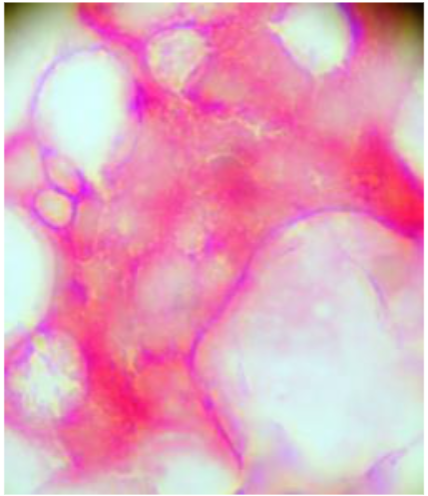

Figure 4: Bone marrow micro-metastasis CEA positive (red) and MMP-2 positive brown). Likewise circulating tumour cells detected in venous blood samples could be negative for the expression of CEA, in other words normal leukocytes, or express CEA and/or MMP-2 (Figure 5).